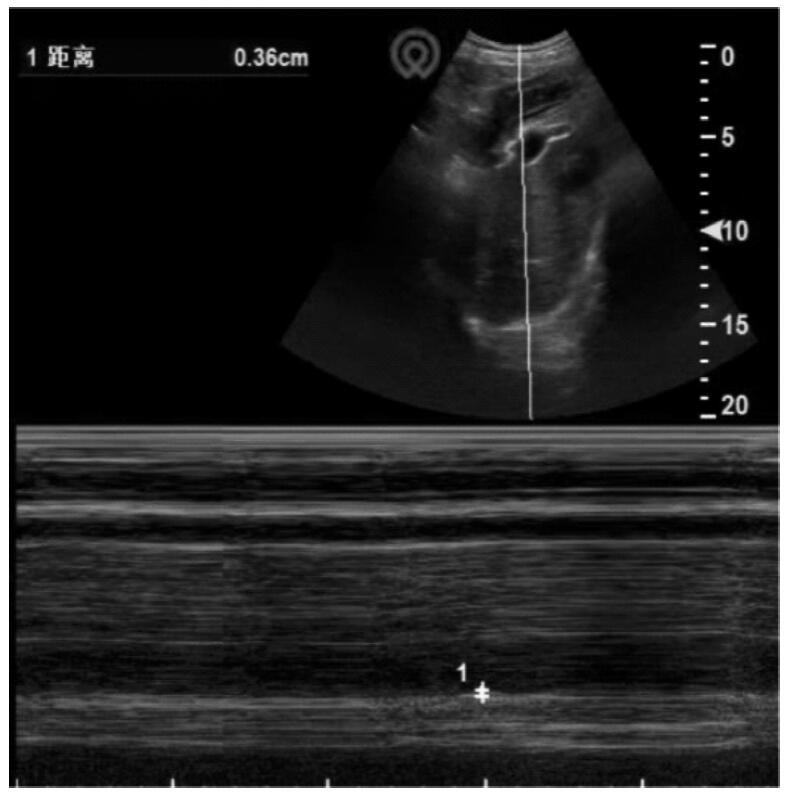

目的:探讨免疫功能正常的重症Ⅰ型单纯疱疹病毒(type Ⅰ herpes simplex virus,HSV-1)肺炎的诊治思路。方法:收集和回顾4例2021年4月至12月入住开云网页登录 医学院附属瑞金医院呼吸重症监护室(respiratory intensive care unit,RICU)诊断为重症HSV-1肺炎患者的诊治过程,并复习国内外相关文献。4例患者均为男性,年龄72~89岁。结果:4例患者以发热、咳嗽、咳痰(部分患者有血性痰)、气喘和呼吸困难为主要症状。患者均出现重度Ⅰ型呼吸衰竭,感染指标均上升,同时淋巴细胞计数相对下降,CD3、CD4、CD8绝对计数在治疗后均出现明显上升。呼吸道标本的宏基因组二代测序(metagenomic next generation sequencing, mNGS)中都检测到HSV-1。所有患者采用早期抗病毒、激素抗炎,呼吸支持治疗后,病情均好转,其中3例治愈出院。文献共检索到免疫力低下的HSV-1肺炎26例,免疫功能正常3例。29例患者的临床症状、体征缺乏特异性,经验性给予抗细菌或真菌治疗无效后,多数进一步完善肺泡灌洗液病原学检查,证实HSV-1感染后,积极给予阿昔洛韦抗病毒治疗,部分患者联合激素治疗,3例免疫功能正常者病情均好转,26例免疫力低下者中22例好转,4例死亡。结论高龄重症HSV-1性肺炎临床表现缺乏特异性,诊断存在一定难度。呼吸道分泌物mNGS检查联合常规实验室检查有助于该病的诊断。早期认识该病,予以抗病毒药物,短程使用糖皮质激素治疗可有效治疗该病。